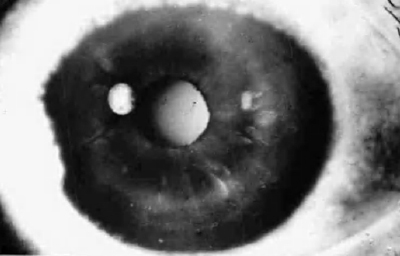

Al examen: OD Edema corneal con Queratopatía bullosa, “Atro a del Iris”, Opacidad subcapsular anterior;. Tensión ocular digital media. Secuelas tóxicas de picadura (Foto No12)

Foto 12 - Foto con edema total de la córnea, despigmentación del Iris y opacidad subcapsular anterior